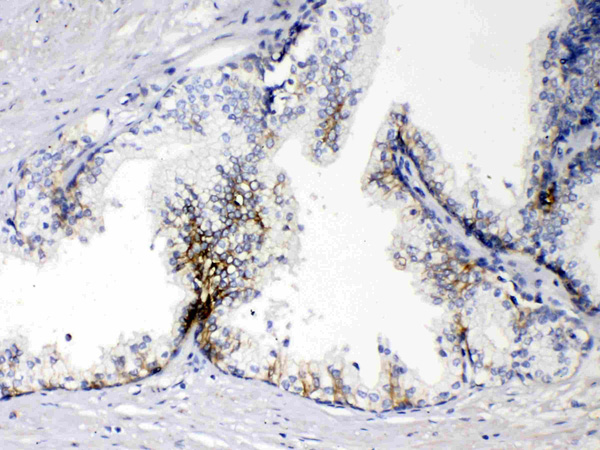

IHC (Immunohistochemisry)

(EPCAM was detected in paraffin-embedded sections of human prostatic cancer tissues using rabbit anti- EPCAM Antigen Affinity purified polyclonal antibody at 1ug/mL. The immunohistochemical section was developed using SABC method.)